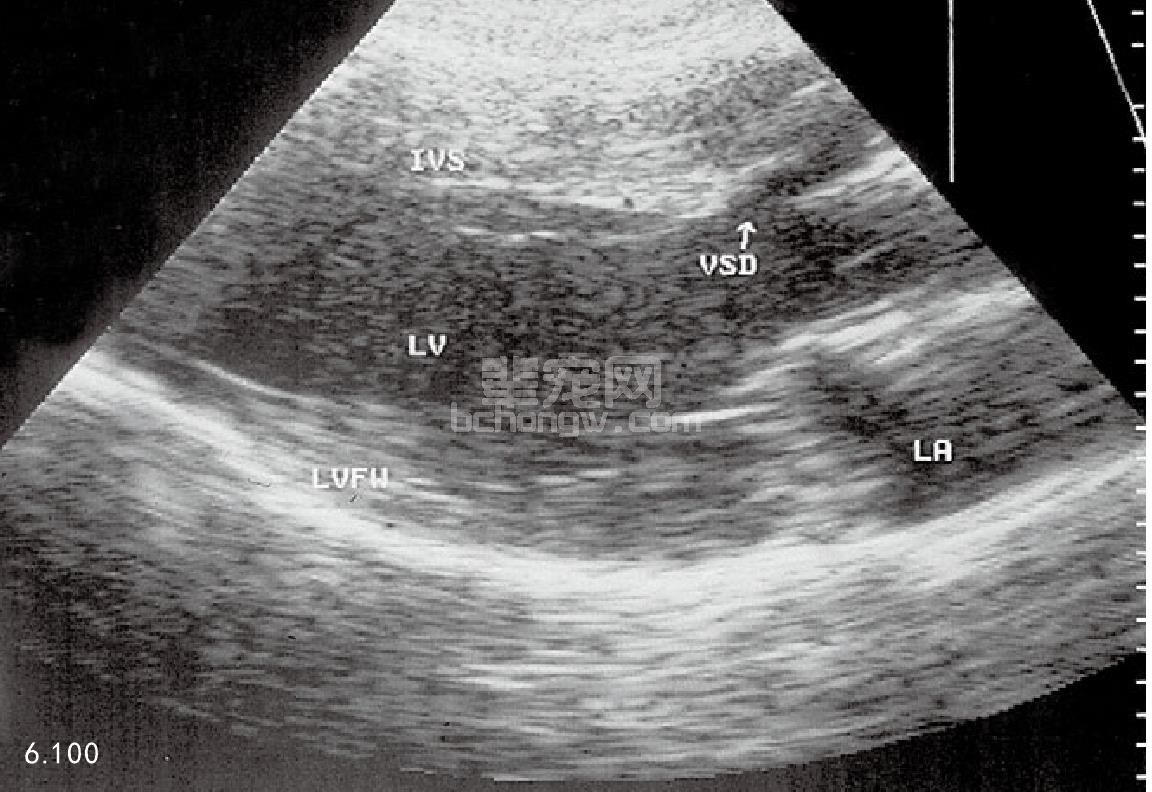

超声波心动描记术 (图6.100和图6.101)左心房和左心室扩张表明血液超负荷。如果缺损较大,则左心室 运动功能亢进。右心室常常变化不明显,但可因具有血液动力学分流的影响而出现扩张。

在主动脉瓣下面,间隔部位的膜状区可见到VSD。通过几张影像平面图来论证缺损非常重要,从而避免因为 回波消失而引起误诊。使用光谱的和彩色流动多普勒仪信号,从而论证靠近隔膜的心室。多普勒超声波心动描记 术,显示了较高的流动速率,并伴有不同程度的紊乱。从左心室到右心室的分流具有支配作用。二尖瓣的回流较 常见。

图6.100 9月龄猫的超声波心动描记,VSD正好在动脉瓣的下面。